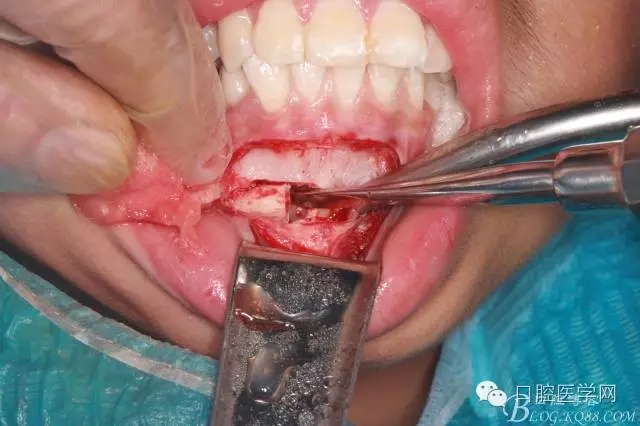

橫位埋伏3的取出術(shù)